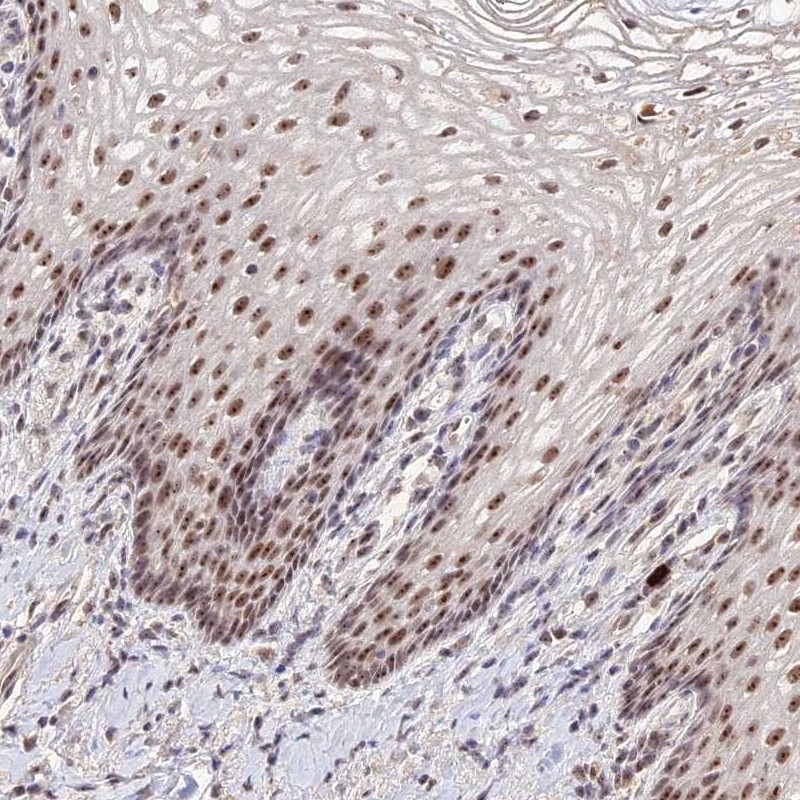

Immunohistochemical staining of human vagina shows moderate nucleolar positivity in squamous epithelial cells.